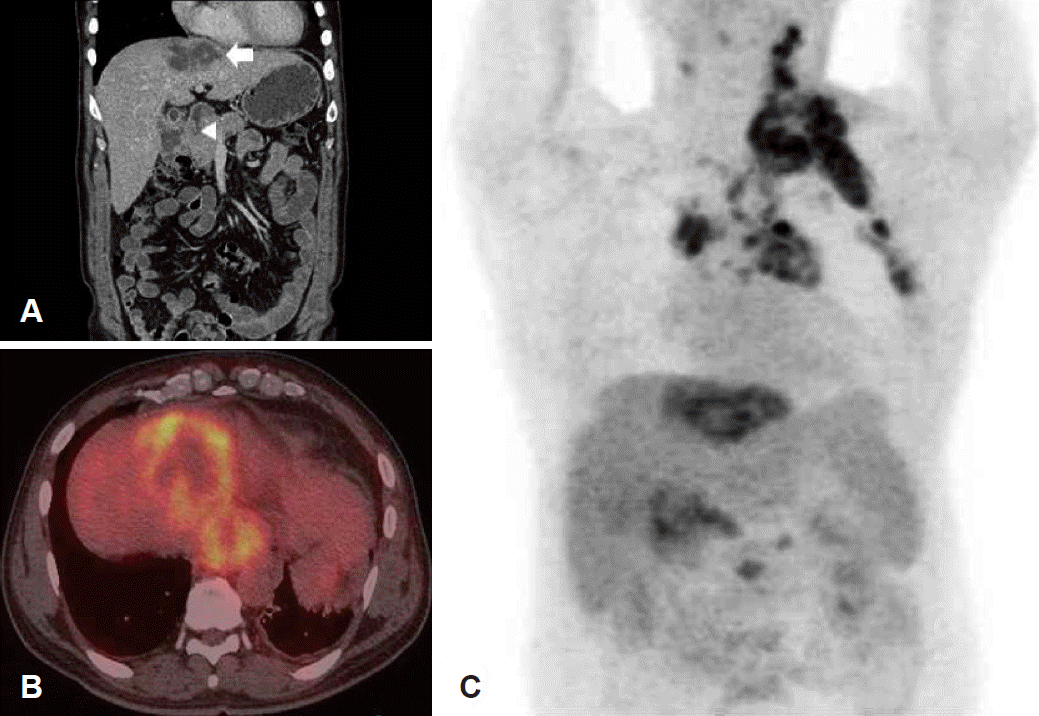

Fig. 3.

Abdominal CT scan shows about 6.5×4.4 cm sized ill-defined mass with the heterogeneous central low density (white arrow) in the right upper lobe of the liver, and the enlargement of paraaortic and pericholecystic lymph nodes (white arrowhead) (A). PET-CT scan shows the uptakes of 18F-FDG at the hepatic dome of the liver and inferior phrenic station with central 18F-FDG defected area (B). PET-CT scan shows the uptakes of 18F-FDG of the multiple lymph nodes at the left cervical level II-V, left axilla, pericholecystic area, and paraaortic area of the mediastinum and abdomen (C). FDG: fluorodeoxyglucose, PET-CT: positron emission tomography-computed tomography.

환자 병력청취 상 경추와 어깨 관절 부위에 스테로이드 주사를 맞은 후에 급격히 커진 압통성 종물이라는 점과 전신 발열의 동반, 급성기 반응 수치의 증가 등을 종합하였을 때 우선적으로 급성 화농성 경부 림프절염을 의심하여 3세대 cephalosporine계와 clindamycin계 정맥 항생제를 투여하였다. 4일간의 정맥 항생제 치료 동안 활력 징후는 정상 범위를 유지 하였으나, 경부 종물의 크기와 압통이 호전되지 않아, 초음파 유도 하 경부 림프절 조직 침생검(ultrasound guided core biopsy)을 시행하였다. 병리조직 검사 결과 상 저분화 악성 종양 소견이 확인되었으나(Fig. 2A), hepatocyte specific antigen(HepPar-1) 면역조직염색을 포함한 여타 특수 염색에서 음성 소견을 보여 정확한 원발 부위를 알 수 없었다(Fig. 2B). 따라서 종양의 분포와 원발 부위 탐색을 위해 양전자 컴퓨터단층촬영(PET-CT)을 시행하였다. 양전자 컴퓨터단층촬영 검사 상 간 우상엽 횡경막 직하부(hepatic dome of right upper lobe)에 중심부 괴사를 동반한 18F-fluorodeoxyglucose (FDG) 흡수가 증가된 병변이 관찰되었으며, 경부 림프절 이외에 횡경막 아래와 담낭 주위, 종격동 대동맥 주위, 복부 대동맥 주위, 좌측 간동맥 주위 림프절에도 18F-FDG 흡수가 증가된 소견이 관찰되었다(Fig. 3). 이후 환자는 소화기 내과로 전과되어 간 세침 흡인 조직검사 시행 후 간세포암으로 확진 되었으며(Fig. 2C), 경구 항암제(sorafenib) 치료를 시작하였으나 점차 악화되는 전신쇠약으로 두 달 후 사망하였다.